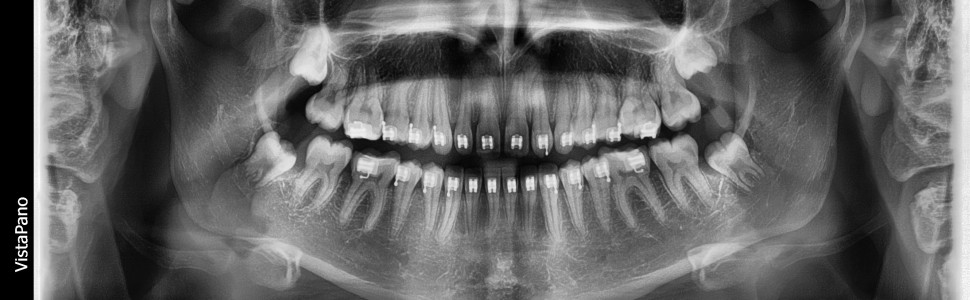

W pracy opisano proces diagnostyczny i zastosowane aparaty ortodontyczne u 13-letniej pacjentki, która zgłosiła się do poradni ortodontycznej z powodu braku zęba w okolicy lewego bocznego zęba siecznego szczęki. Dokumentacja radiologiczna wykazała pełną transpozycję kła i bocznego zęba siecznego szczęki oraz obecność przetrwałego kła mlecznego po stronie lewej. Brak miejsca w łuku doprowadził do zatrzymania stałego lewego kła oraz do nieznacznego przesunięcia linii pośrodkowej w górnym łuku w stronę lewą. Pacjentka leczona była z zastosowaniem aparatów stałych, nie było konieczności wspomagania chirurgicznego przy sprowadzaniu zatrzymanego kła. Z uwagi na ryzyko resorpcji korzeni zębów oraz blaszki zbitej wyrostka zębodołowego nie przywracano prawidłowej kolejności zębów objętych transpozycją.

The article describes the diagnostic process and orthodontic appliances that were used in a 13-year old female patient who came to orthodontic clinic due to a missing tooth in the area of the left lateral incisor of the maxilla. Radiological documentation showed complete transposition of the canine and maxillary lateral incisor and the presence of a persistent deciduous canine on the left side. The lack of space in the arch led to the retention of the permanent left canine and to a slight shift of the midline in the upper arch to the left. The patient was treated with fixed appliance, there was no need for surgical assistance in bringing back impacted canine into normal position. Due to the risk of resorption of tooth roots and the cortical plate of the alveolar process, the correct order of the transposed teeth was not restored.